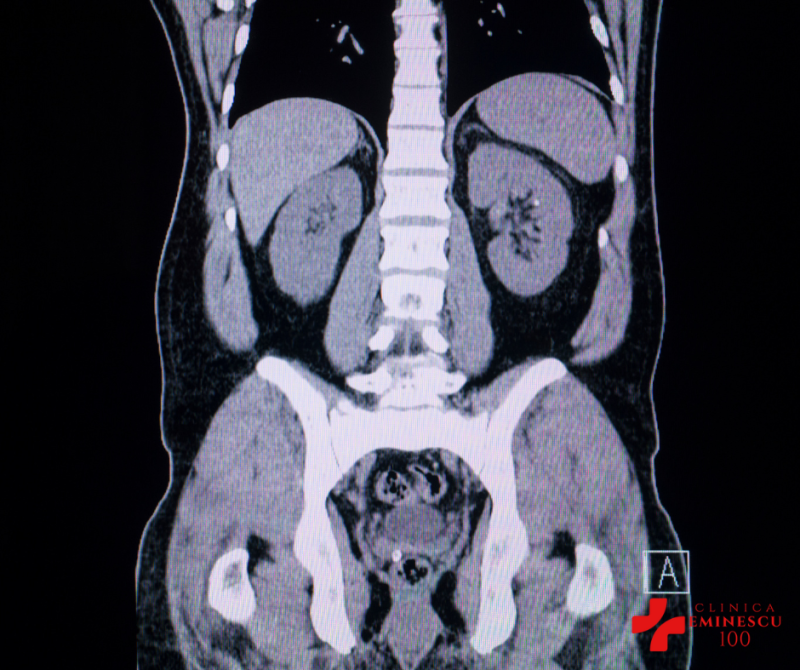

- CT

- CT